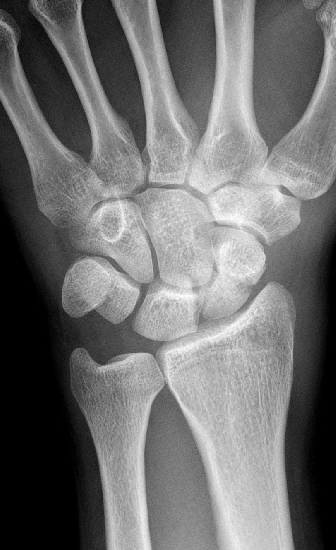

1. Bei der ersten Untersuchung handelt es sich um

- a) eine pa-Aufnahme des Handgelenkes

- b) eine Seitaufnahme des Handgelenkes

- c) eine Schrägaufnahme des Handgelenkes

- d) eine pa-Aufnahme des Vorfußes

- e) eine Seitaufnahme des Vorfußes

5) Was notieren sie in Ihrem Befund?

- a) Lunatum-Splitterfraktur

- b) Capitatum-Längsfraktur

- c) Skaphoid-Querfraktur

- d) Radius-Flexionsfraktur

- e) Radius-Extensionsfraktur

Warum ist es wichtig bei einer Kahnbeinfraktur zu notieren ob die Fraktur im proximalen oder distalen Drittel lokalisiert ist?

- a) Die Durchblutung des Kahnbeins erfolgt von distal, daher neigen proximale Frakturen eher zu Pseudarthrosen.

- b) Die Durchblutung des Kahnbeins erfolgt von proximal, daher neigen distale Frakturen eher zu Pseudarthrosen.